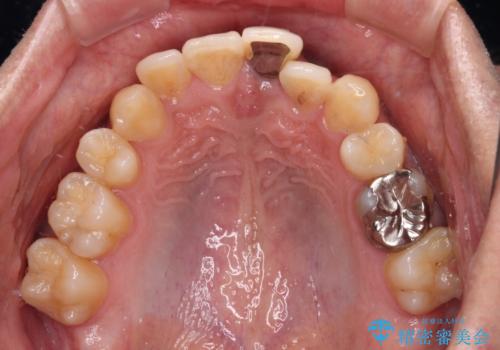

- 下顎の八重歯を気にして来院された患者様です。

左下以外、3本の第一小臼歯が既に抜去されており、左下は八重歯になっている状態でした。

左下の八重歯は手前に傾斜していたため、インビザラインによる抜歯矯正が可能と判断し、後方にある第一小臼歯を抜歯してインビザラインにて矯正治療を行うこととしました。

ワイヤー矯正と比較すると、八重歯が後方に傾斜した仕上がりとなりましたが、患者様ご希望のインビザラインにて十分な歯列を達成することができました。